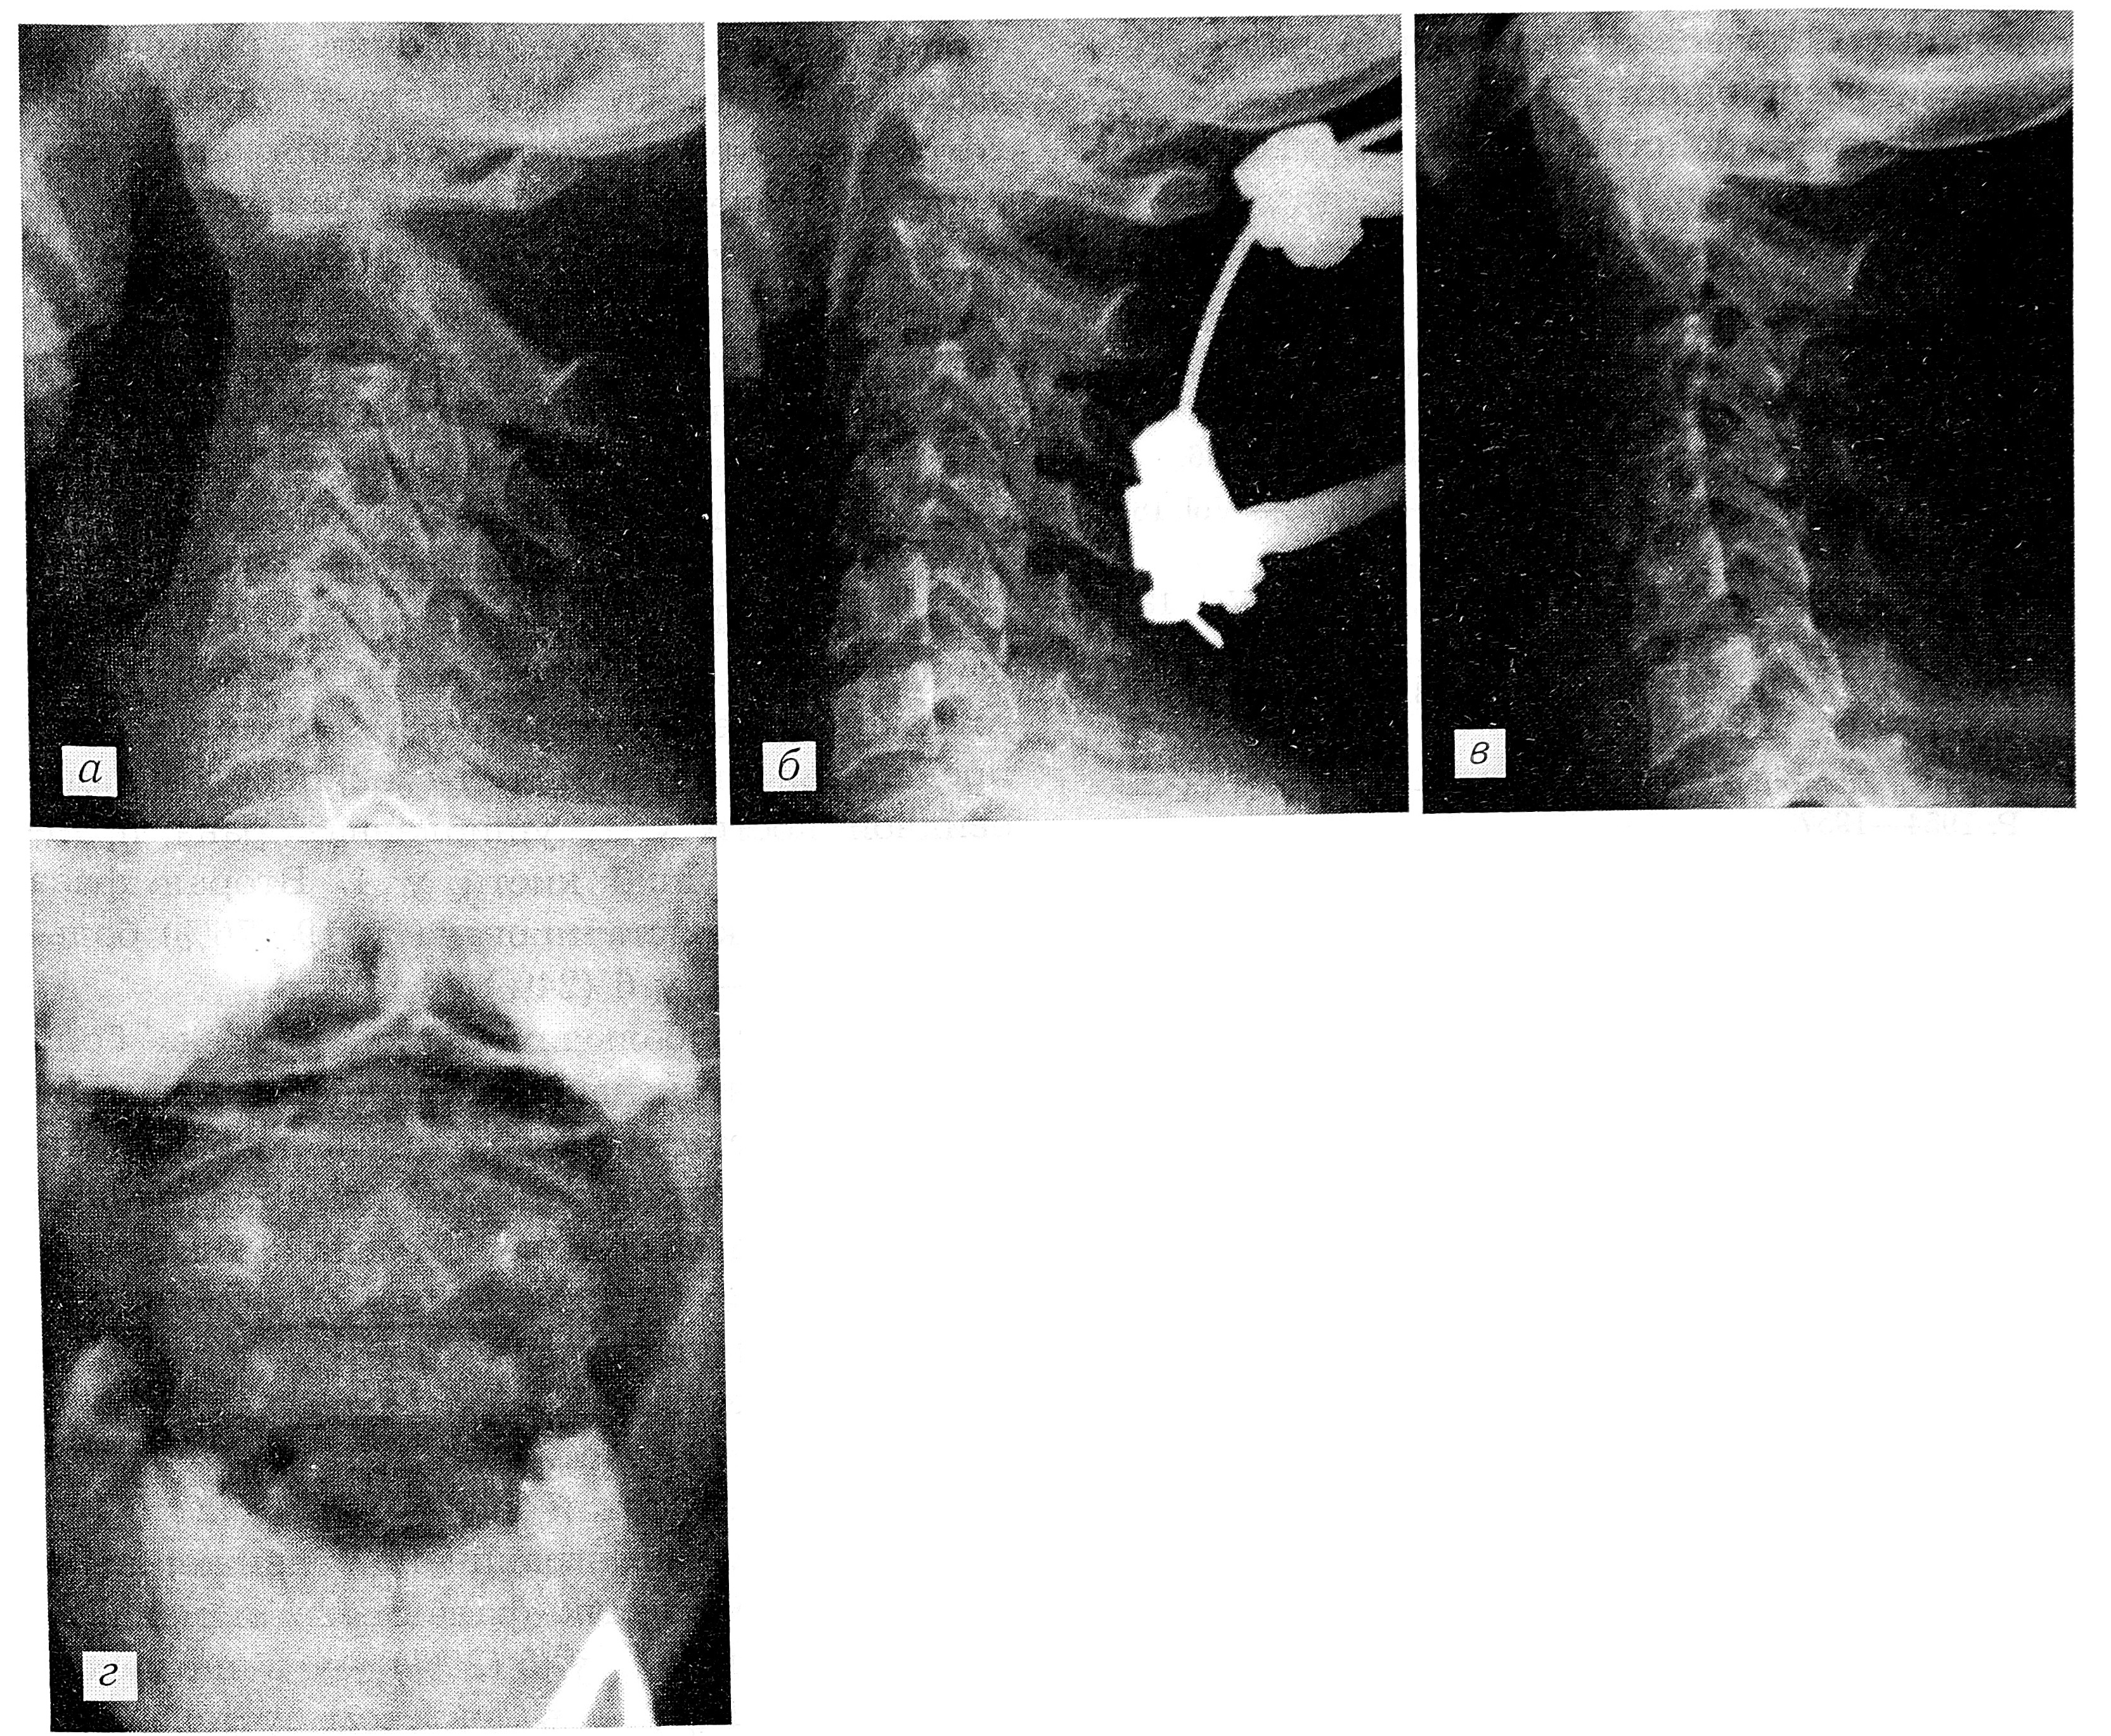

Рентгенограммы шейного отдела позвоночника больной Г. а — при поступлении: перелом зубовидного отростка С2 со смещением отломков на весь поперечник; б — шейный отдел фиксирован в гало- аппарате, дополнительно проведена спица через остистый отросток С2 достигнута полная репозиция; в — через 3 мес: достигнута полная консолидация перелома; г — снимок, выполненный через рот: хорошо видна массивная костная мозоль.

Больная Г., 27 лет, получила травму шейного отдела позвоночника в автоаварии. Машиной скорой помощи была доставлена в городскую больницу. Произведена рентгенография шейного отдела позвоночника, перелом зубовидного отростка не выявлен, и больная с наложенным воротником Шанца отпущена домой для наблюдения по месту жительства. Через 2 нед самостоятельно сняла воротник и длительное время ходила без всякой иммобилизации. Постепенно боли в шейном отделе позвоночника стали усиливаться, нарастало ограничение движений в нем. В связи с этим спустя 2 мес после травмы больная обратилась в травматологический пункт. Повторно произведена рентгенография шейного отдела позвоночника и диагностирован перелом зубовидного отростка с передним трансдентальным вывихом атланта (см. рисунок, а).

На рентгенограммах шейного отдела позвоночника определяется застарелый перелом основания зубовидного отростка С2 позвонка. Атлант вместе с отломком зубовидного отростка смещен кпереди на весь поперечник.

Больной был наложен аппарат для гало-тракции и в течение 2 нед осуществлялось дозированное вытяжение шейного отдела позвоночника. Отломки были растянуты, но оставалось смещение по ширине. Вторым этапом через остистый отросток С2 проведена спица, которая затем натянута в скобе, скоба подсоединена к штангам гало-аппарата. За счет создания упора в остистый отросток и тяги за него достигнута полная репозиция отломка (см. рисунок, б). Гало-аппарат зафиксирован в этом положении. Через 3 мес на контрольных рентгенограммах выявлена полная консолидация перелома (см. рисунок, в, г). Аппарат снят. В течение 2 нед больная ходила в головодержателе из вспененного полиэтилена. Контрольный осмотр через месяц: жалоб нет, отмечается лишь небольшое ограничение движений в шейном отделе позвоночника.